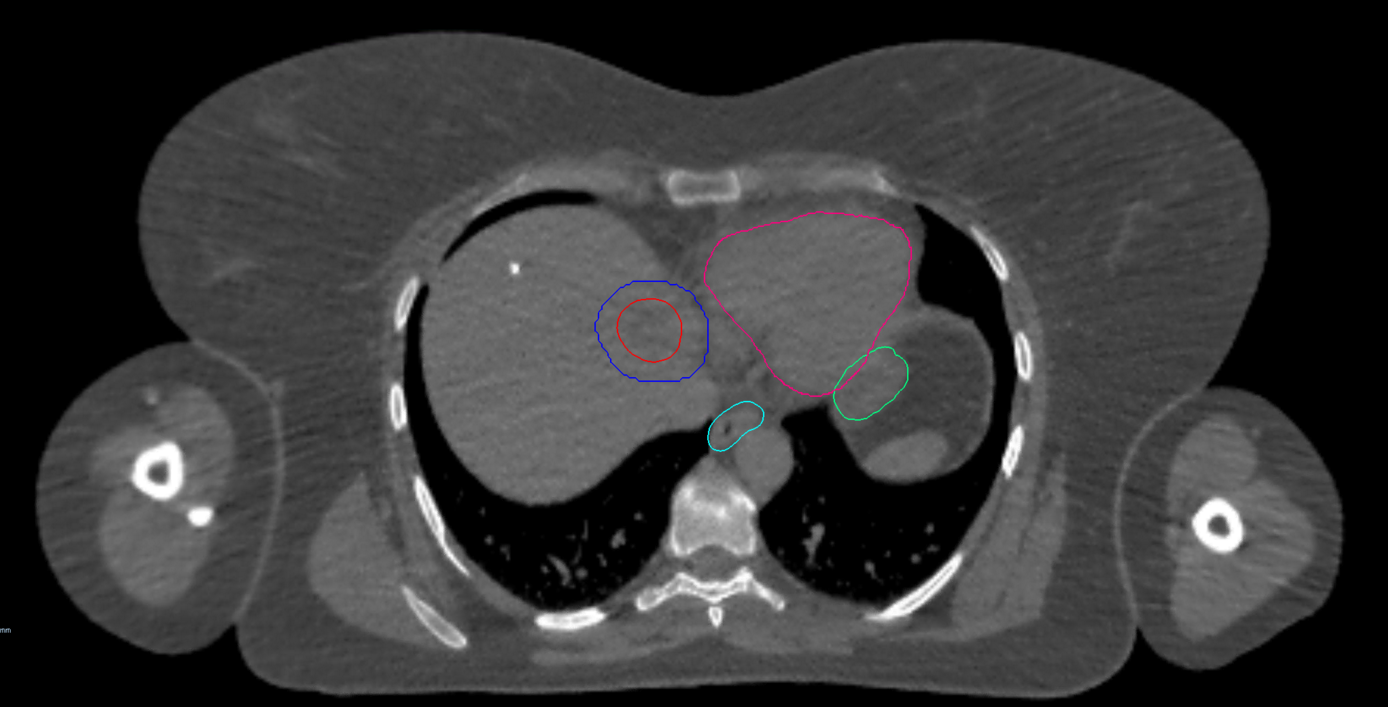

Right Central Lung Metastasis

< View All Plan Studies CYBERKNIFE SYSTEM Right Central Lung Metastasis Case History AGE: 62-year-oldGENDER: Male Medical History Chronic obstructive pulmonary disease (COPD), previous surgery on right lung Chest CT: Suspicious lesion in the right lower lobe PET-CT: hypermetabolic nodule, 3.1cm no evidence of regional or distant metastasis Non-Small Cell